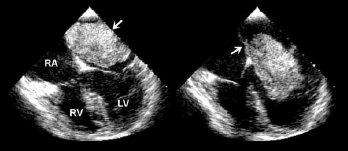

Sobre a patologia exibida nas seguintes imagens, é correto afirmar que

Provas